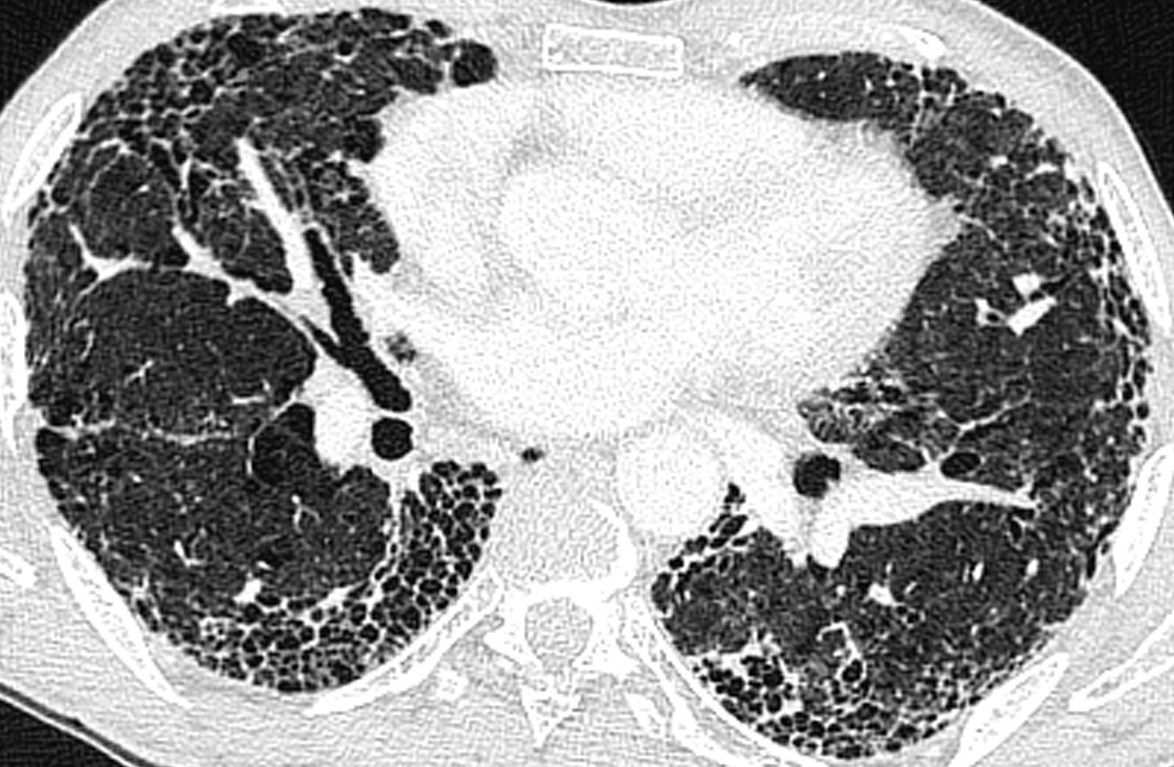

La radiographie de thorax est la suivante.

Figure 1.

Question 1 - Qu’est-il possible d’affirmer d’après la radiographie de thorax (une ou plusieurs réponses exactes) ?

Prédominance de réticulations de manière diffuse.

Culs de sac pleuraux bien visibles.

Absence de cœur en goutte, d’aplatissement des coupoles et d’horizontalisation des côtes.

Un syndrome interstitiel est évoqué sur la radiographie thoracique devant la présence de réticulations diffuses majoritairement. Ces traits sont orientés dans toutes les directions, pouvant dessiner ainsi des polygones correspondant aux lobules pulmonaires.

Le syndrome interstitiel radiologique peut être composé de :

– réticulations (« traits » correspondants aux septa lobulaires) ;

– micronodules (< 3 mm) ;

– épaississements péribronchovasculaires ;

– verre dépoli.